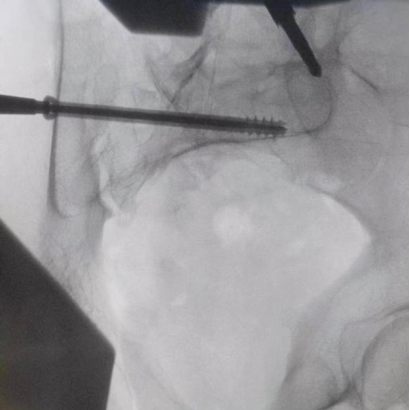

透视下见置入的骶髂螺钉,位置、长度精准,无丝毫偏差